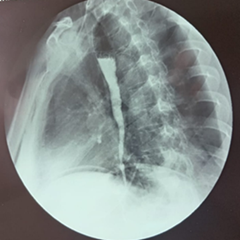

The patient was discharged 72 hours after surgery with instructions to follow a strict liquid diet, divided into 20 small portions per day, until her follow-up appointment. Seven days later, she reported difficulty eating and was advised to continue the liquid diet for an additional 45 days. A gradual transition to a soft diet followed, consisting of approximately 15 small meals per day for a further 30 days, while avoiding hard foods, lean meats, citrus fruits, spicy foods, hot dishes, and alcohol. Twelve months after surgery, the patient transitioned to a general diet, continuing to avoid foods known to trigger esophageal spasm or irritation, such as citrus fruits, spicy or acidic foods, and alcohol (Figure 4).

Postoperative findings in esophageal achalasia.